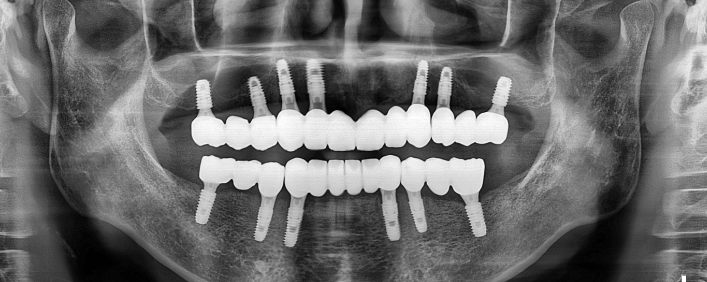

전악 임플란트

치아가 전혀 없거나 소수일 경우, 임플란트를 이용하여 전체 치아를 복원해주는 시술입니다.

자연치아는 위/아래 14개씩 모두 28개가 존재합니다.

자연치아가 상실될 경우, 본래의 치아처럼 회복하기 위해 다수의 임플란트를 식립해야 합니다.

전악 임플란트는 큰 범위의 시술인 만큼 많은 수술 경험으로 기술과 노하우가 필요합니다.